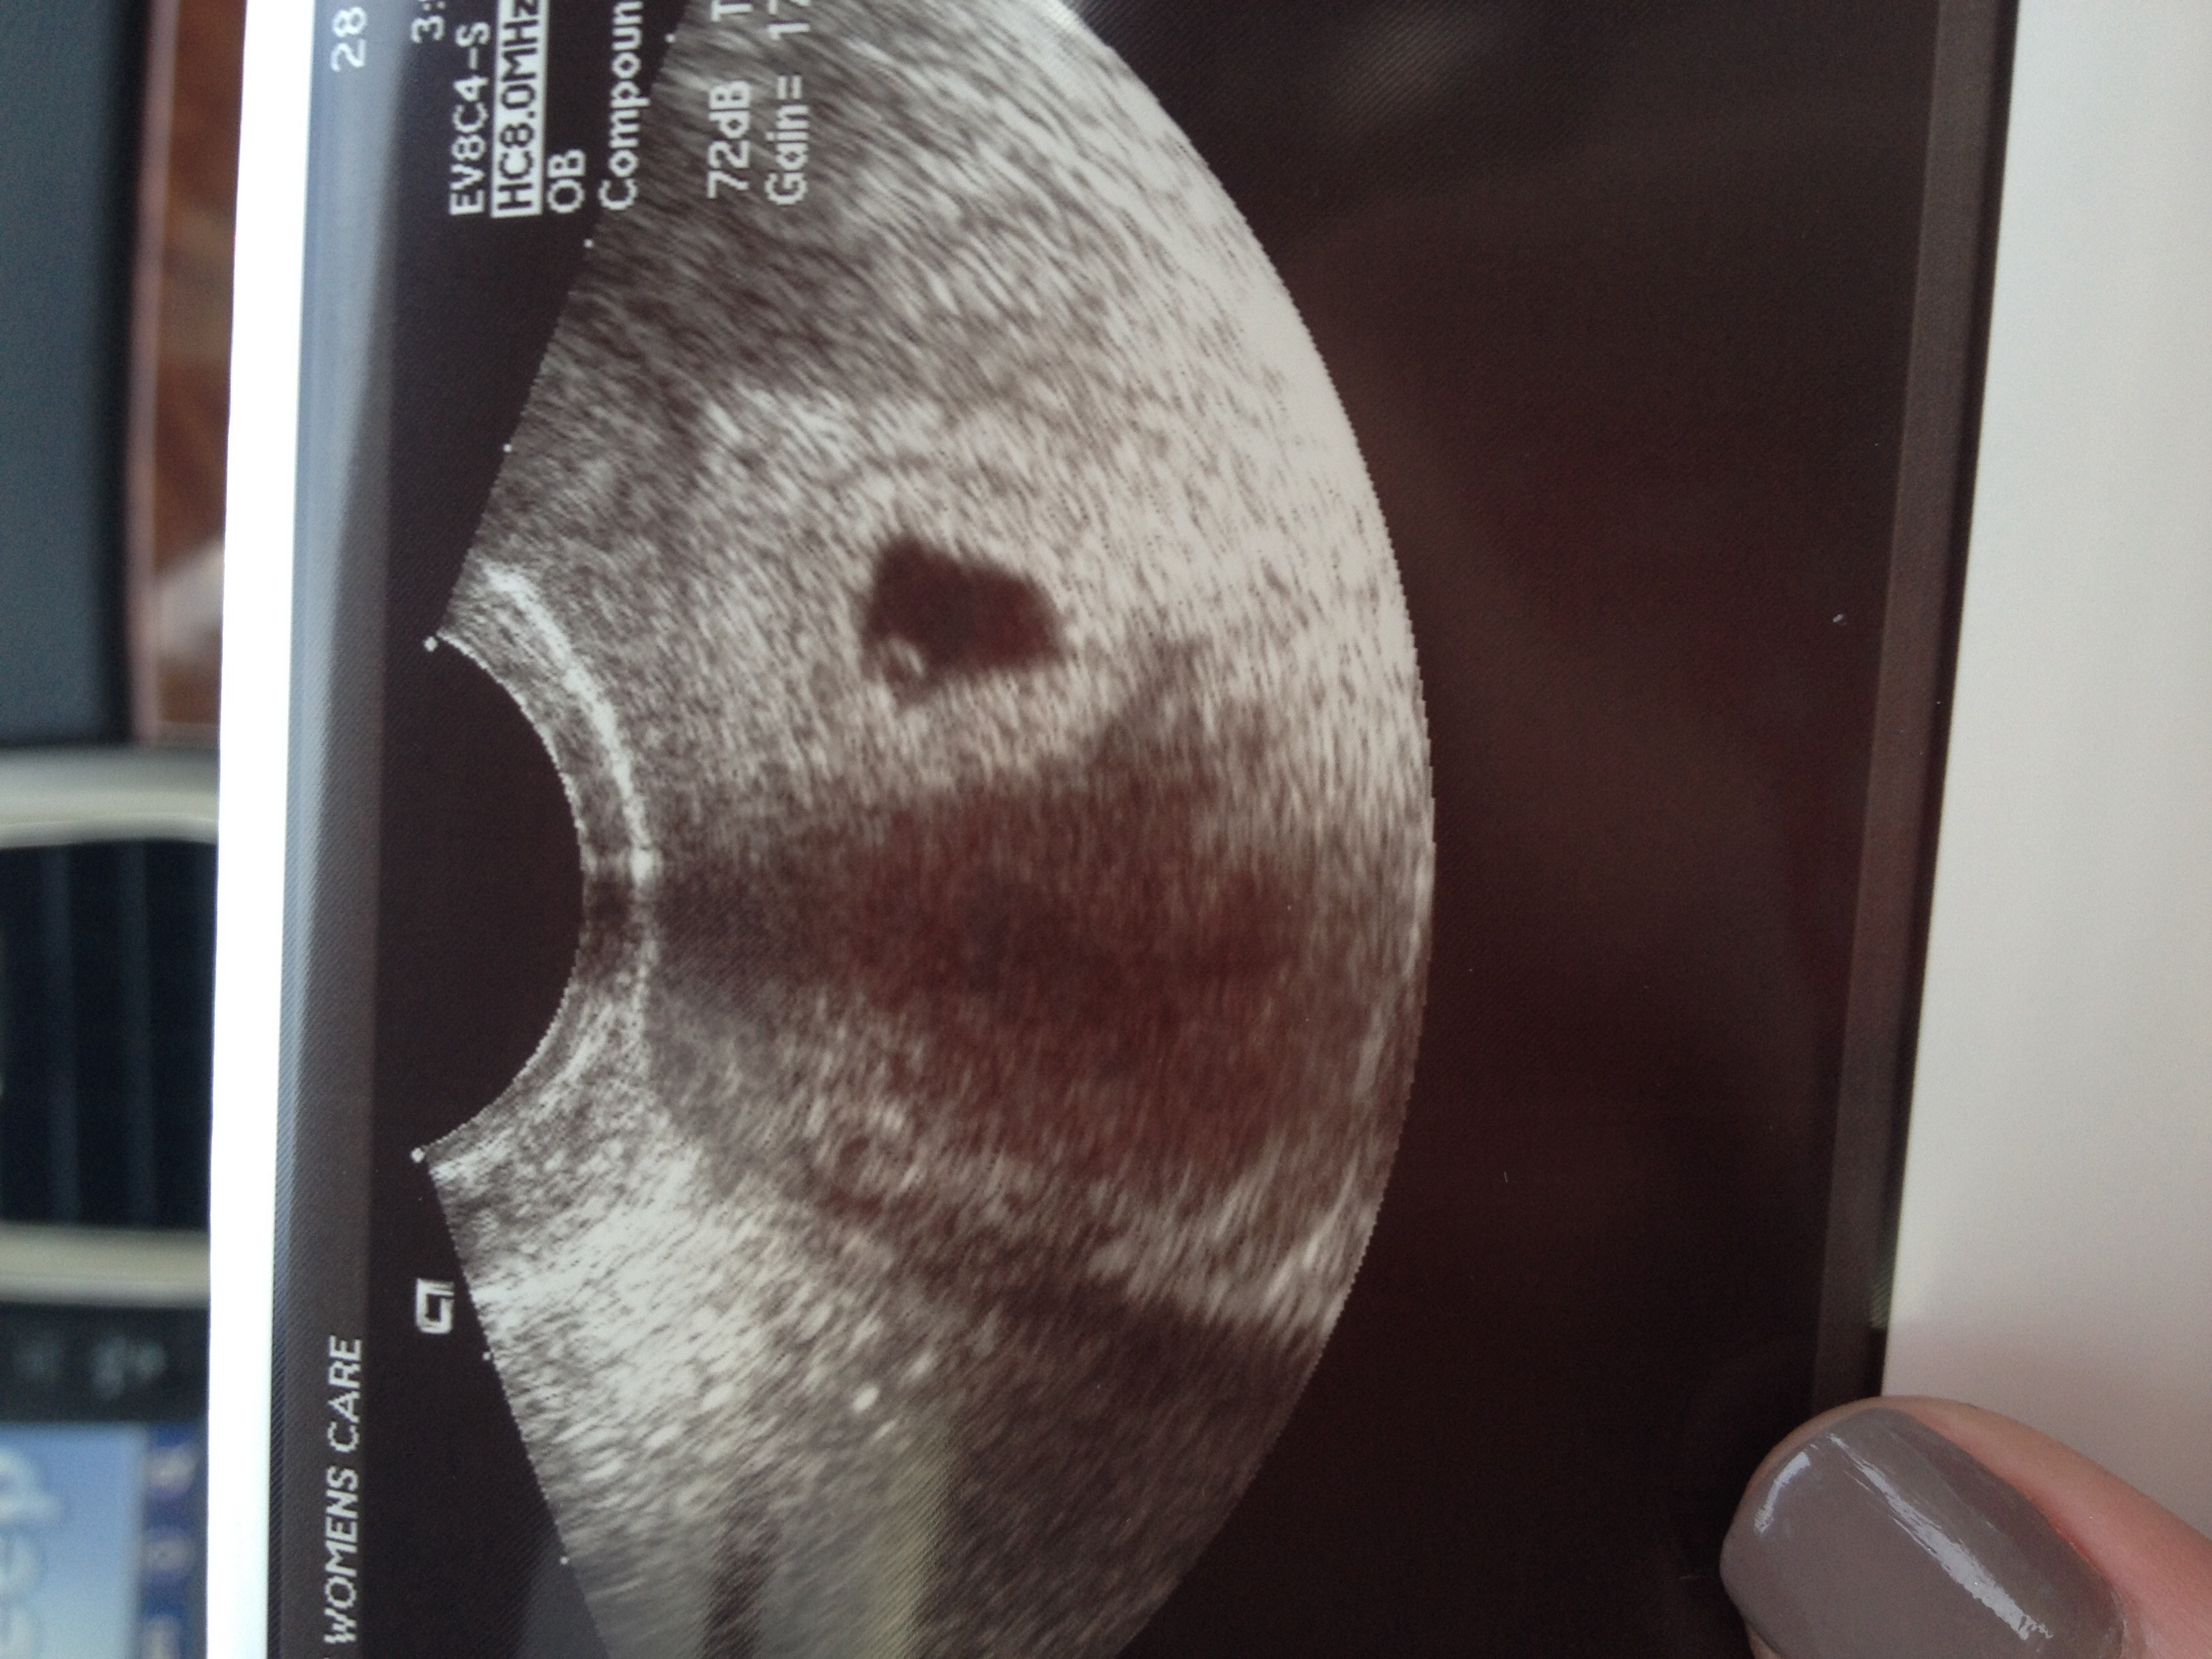

Had my first last night @ 6+1, too small to see anything, but definitely in the uterus and no cause for my spotting seen. OB said I looked more like 5 weeks. Spotting has since stopped (yay!) will repeat it November 3. Beta went from 4100 on Tues to 7100 yesterday, so I feel a bit of reassurance but will certainly feel better when I can see a heartbeat and fetus